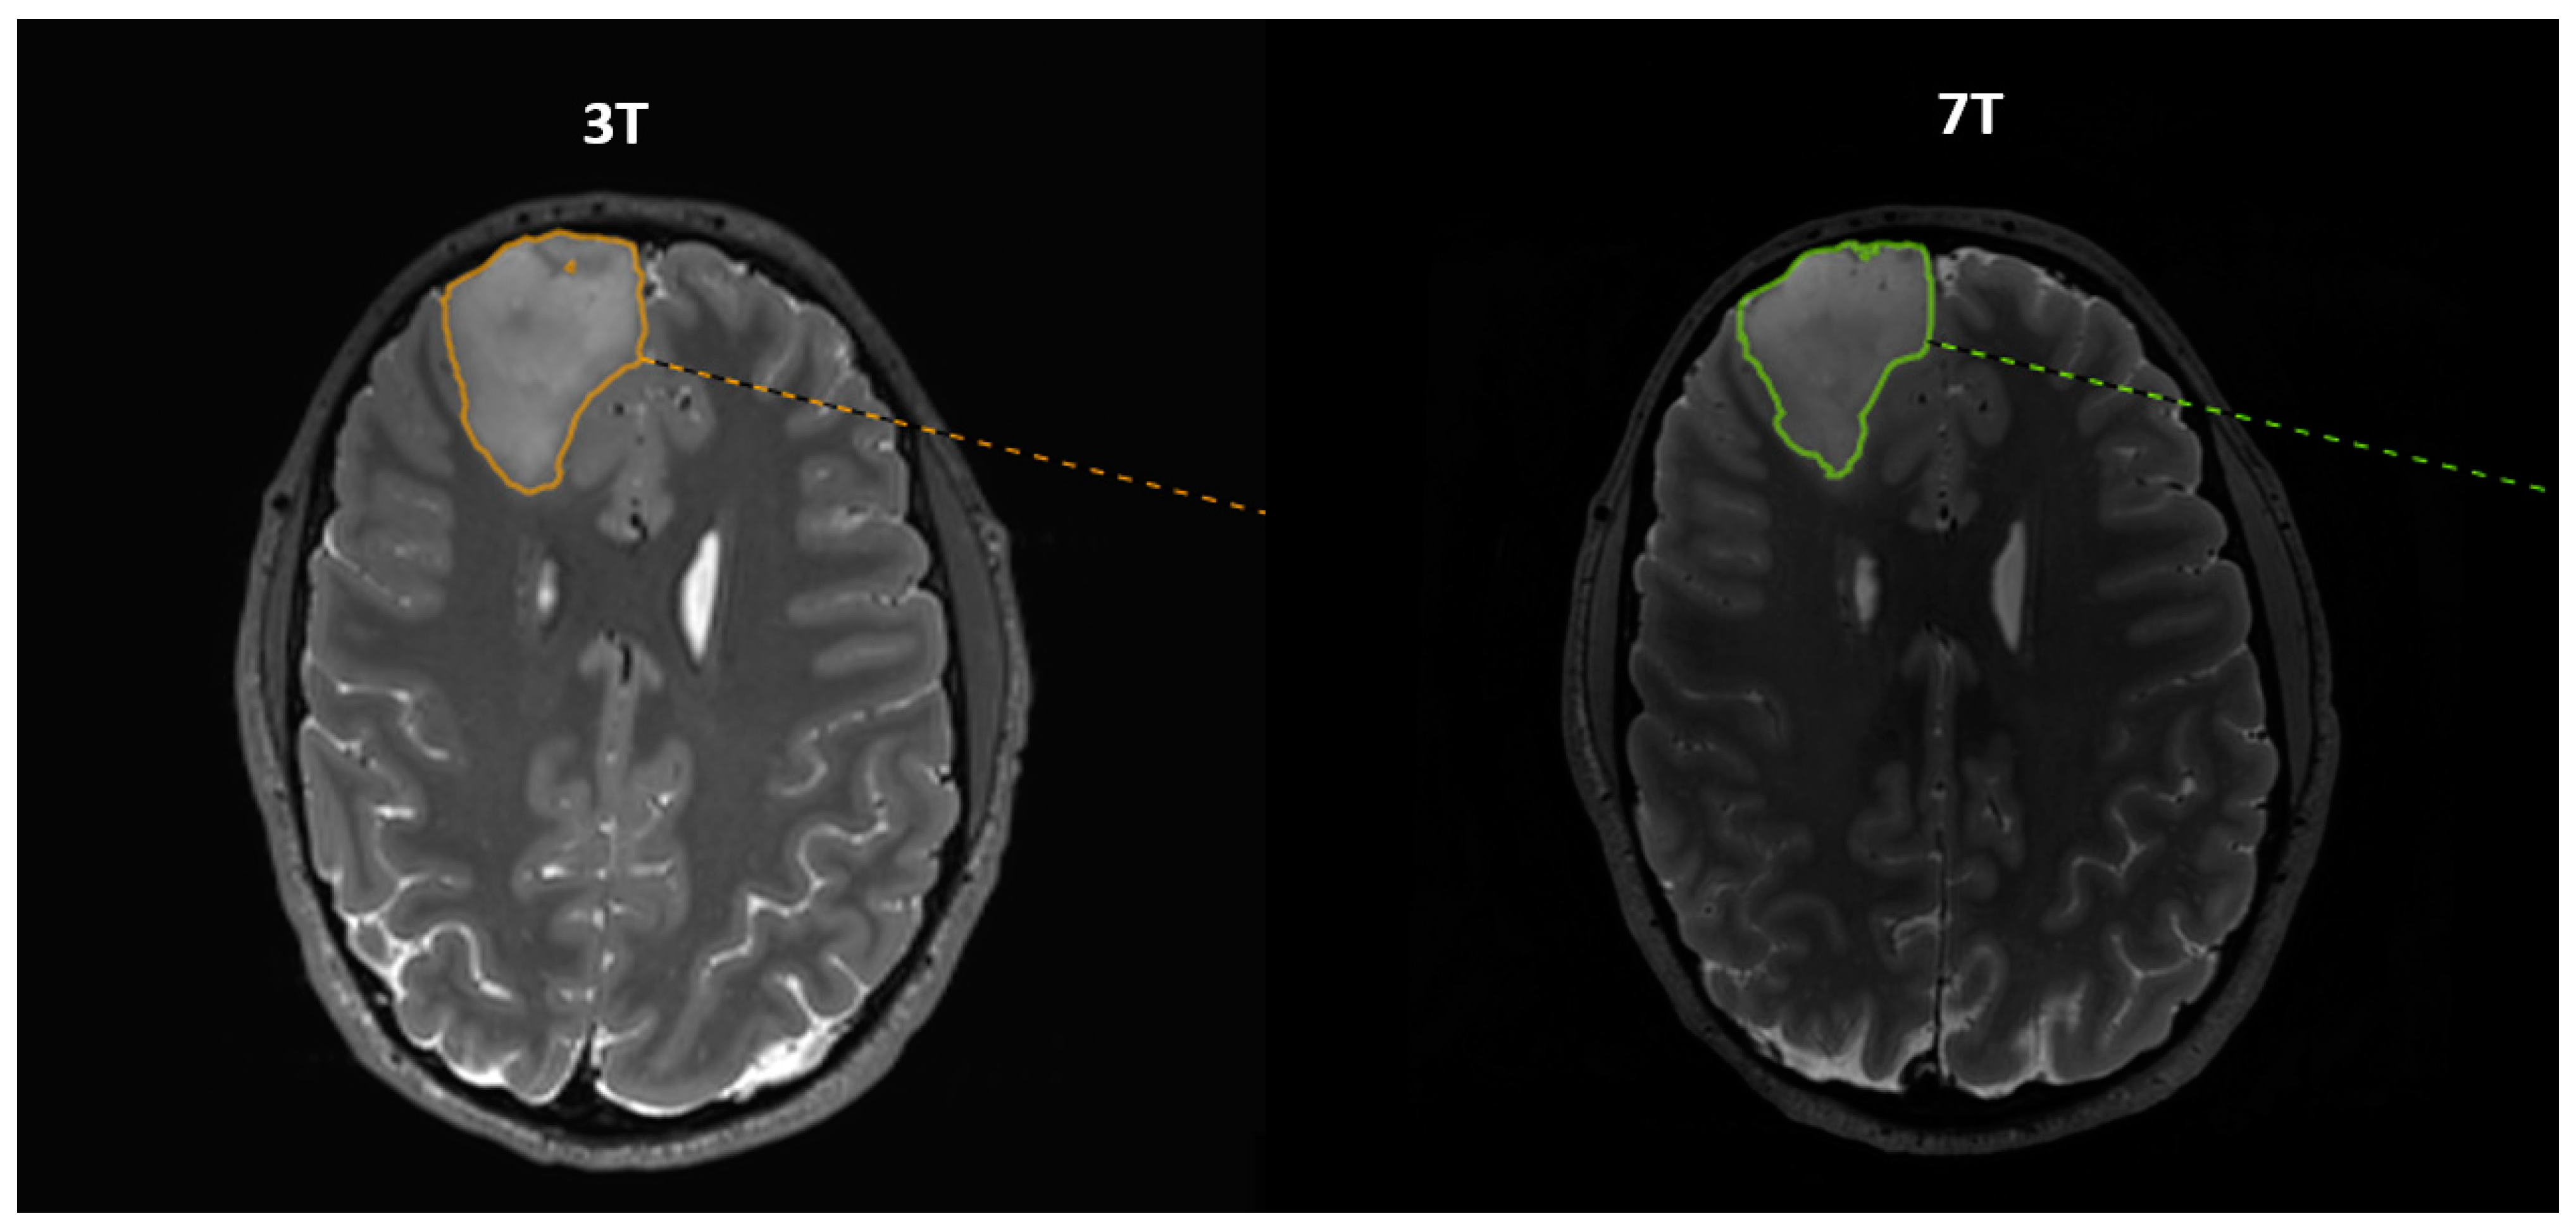

This study was set up as an inter-observer study in which two observers with different clinical backgrounds (medical student/newly educated physician, M.P., (observer 1) and neuroradiologist, J.C., (observer 2)) performed semi-automatic delineations of GTV using Mirada (Mirada Medical Ltd., Oxford, UK). The tumor border was defined visually. Each observer performed the volume delineation once. There were no hurdles while handling the 7T data using the Mirada software. To minimize bias, the two observers were blinded to the results of the other observer until all data sets were acquired and the delineations completed. The order of the structural MR images in which delineations were performed was randomized for observer 2. Observer 1 performed the delineations as soon as data were available. An example of delineations on both 3T and 7T MR images 3D TSE T2 is shown in Figure 1. The difference in GTV from 3T to 7T was calculated in percentage as (GTV3T − GTV7T)/GTV3T. It was categorized into three groups: larger, same, and smaller. The same size was defined at ±5%. The data were further stratified into subgroups such as WHO grade, size (“Big” and “Small” tumor with a cut-off of 15 cm3), and histopathology. Further, we calculated the intraclass correlation coefficient (ICC), which is a measure of reliability between different observers expressed as a number between 0 and 1, with 0 meaning zero reliability and 1 meaning perfect reliability. The average volume size and the average difference between the GTV delineated by the two observers were also calculated both as absolutes and in relative units as (GTVobs1 − GTVobs2)/GTVobs2.

Figure 1.

Corresponding axial slices from 3T and 7T 3D T2 images with delineation of a frontal tumor. The patient was a 35-year-old male with DLGG grade III situated in the right frontal lobe. The slices depict the largest cross-section of the tumor. Of note, the 3T and 7T slices are not completely identical due to slightly differing angulations during the reconstruction of axial images.